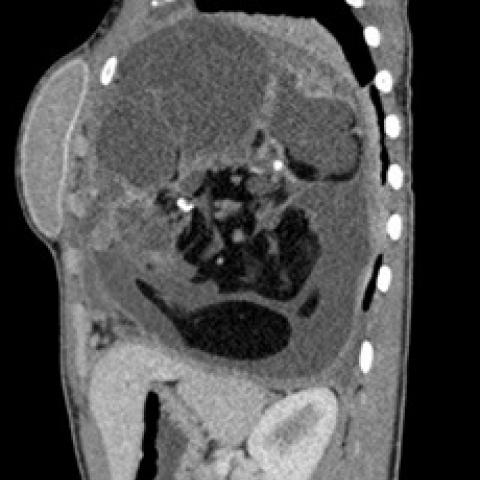

随后进行胸部对比增强CT(计算机断层扫描),结果显示非常大的团块占据左肺大部分,并且左上叶保留。团块由软组织组成,具有肉眼可见的脂肪灶,液性变薄的囊性区和多个钙化灶。CT进一步证实了纵隔移位的程度和左胸腔存在积液。纵隔淋巴结无明显肿大,无骨性病变,无肺扩张。组织学证实有大量成熟的肺内畸胎瘤。

图3矢状面CT显示,左肺内存在大量软组织团块,包括肉眼可见的脂肪、液性变薄的囊性区和多个钙化灶。少量胸腔积液,纵膈移位。